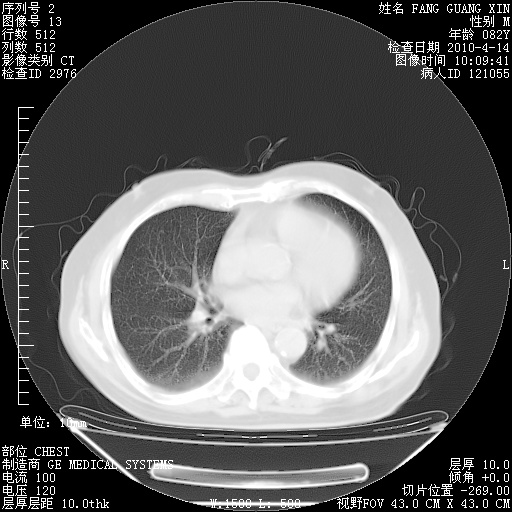

4月14日肺部CT

楼主| 发表于 2010-4-28 16:51 | 显示全部楼层

楼主| 发表于 2010-4-28 16:53 | 显示全部楼层

肺部CT平扫未见异常。